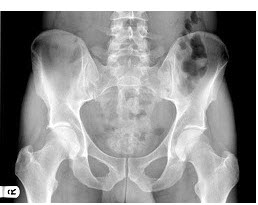

165、单项选择题

男,根据其正常骨盆影像图像,判断其最可能的年龄()

A.68岁左右

B.58岁左右

C.18岁左右

D.48岁左右

E.28岁左右

185、单项选择题

女,根据其正常骨盆影像图像,判断其最可能的年龄()

A.53岁左右

B.13岁左右

C.73岁左右

D.33岁左右

E.63岁左右

211、单项选择题

A.2岁左右

B.5岁左右

C.8岁左右

D.11岁左右